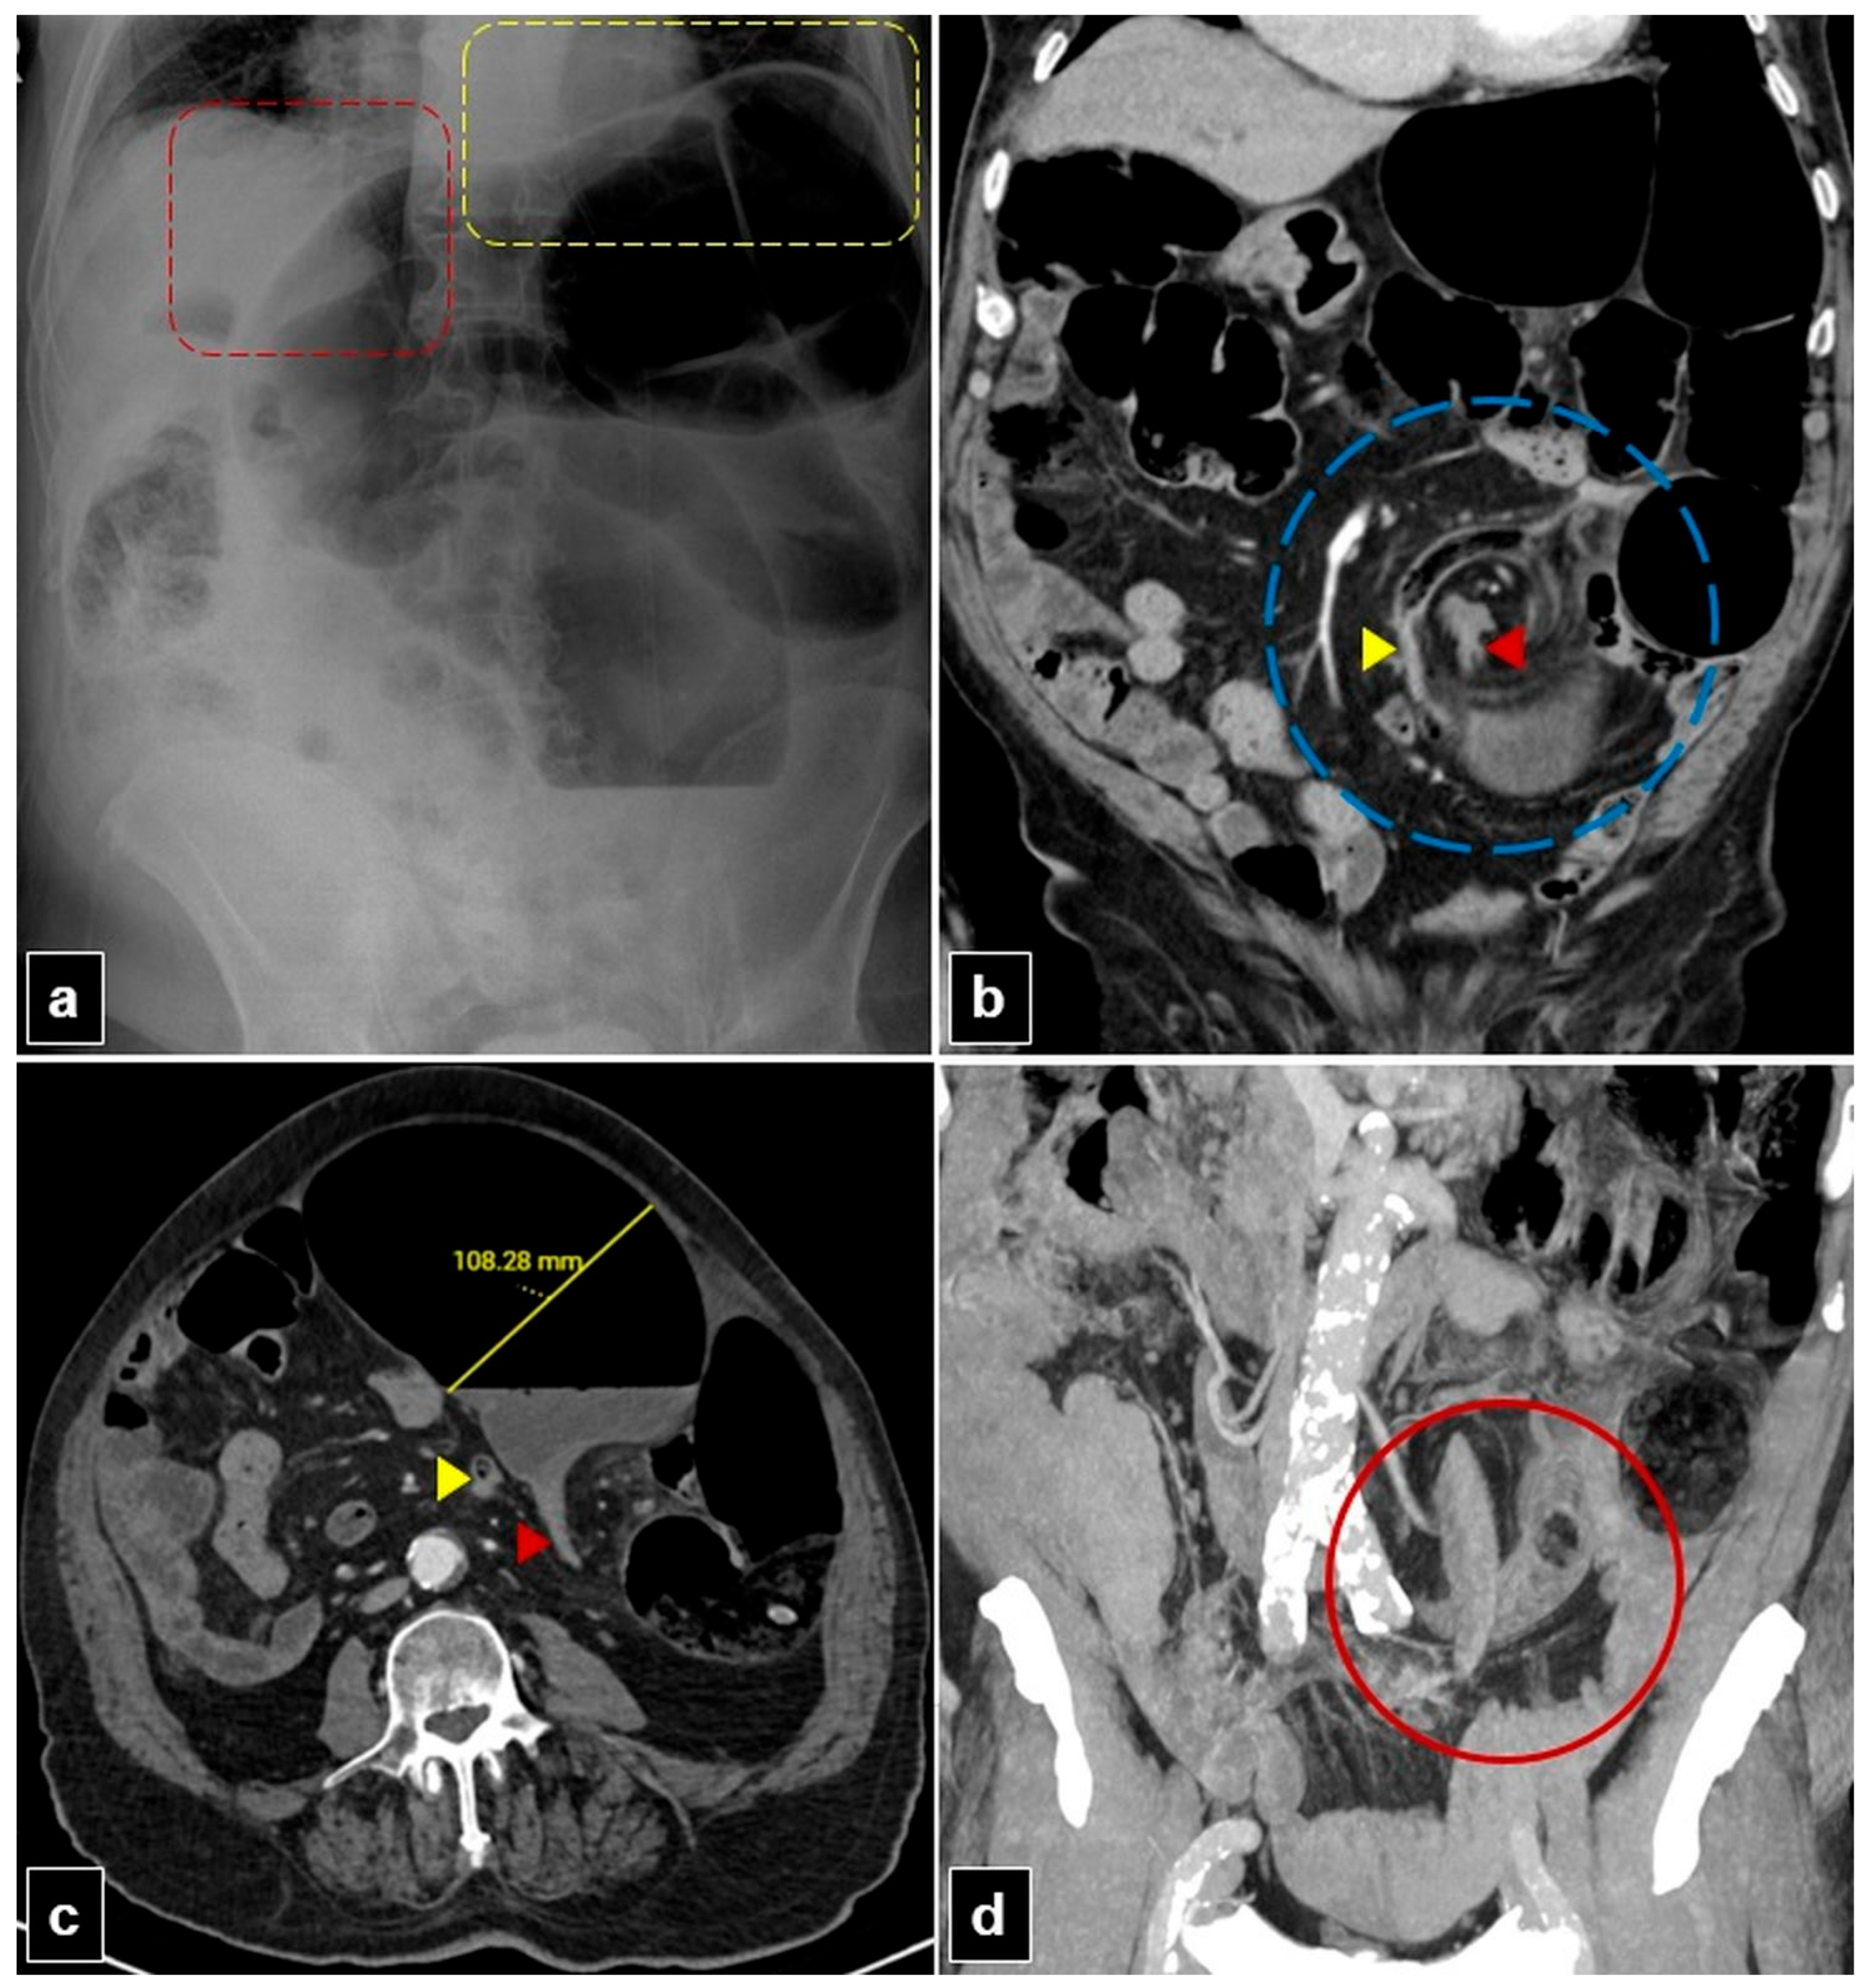

Figure 3. An 80-year-old male patient with a mesentero-axial sigmoid volvulus presented with abdominal pain and constipation for seven days. (a) The plain abdomen radiograph reveals significant distension of the sigmoid loop, characterized by an inverted “U” shape, absence of rectal air lucency, the northern exposure sign, liver overlap sign (red dashed quadrilateral), and the sigmoid apex located beneath the left hemidiaphragm sign (yellow dashed quadrilateral). (b) The coronal plane abdominal computed tomography (CT) image reveals the mesenteric whirlpool sign (blue dashed circle) and transition zones located proximally (yellow arrowhead) and distally (red arrowhead) to the rotating sigmoid loop. (c) The axial plan abdominal CT image shows the degree of distension in the sigmoid colon and the transition zones situated proximally (yellow arrowhead) and distally (red arrowhead) to the rotating sigmoid loop. (d) The coronal plane maximum intensity projection (MIP) CT image of the abdomen shows an x-marks-the-spot sign (red circle) created by the proximal and distal transition zones.